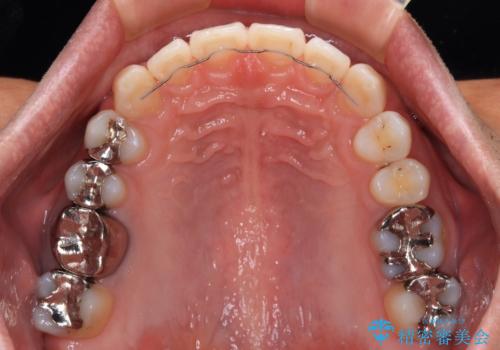

深い咬み合わせと前歯の隙間 ハーフリンガルによる矯正治療

- 矯正装置

- ハーフリンガル

矯正治療中に結婚式があったそうですが、隙間も改善しており、一部装置を外すことなく挙式できたとのことでした。